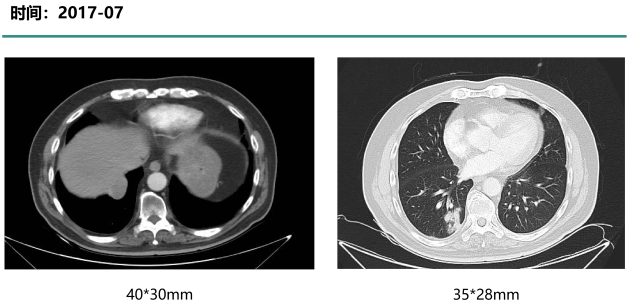

诊疗经过-2

2017-07-25—

二线:CM082+依维莫司

影像学评估—最佳评效 PR

影像学评估